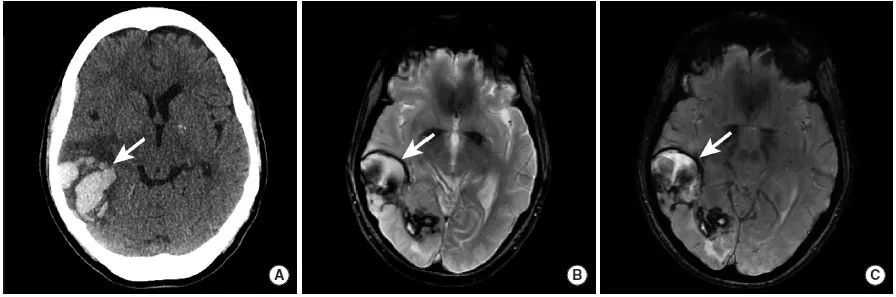

图8

本例患者的CT平扫(图A)、MRI的GRE(图B)和SWI(图C)序列显示右颞叶和枕叶的脑实质内出血(长尾箭头)。这种出血的典型表现是脑叶出血,并不限于动脉的供血区域。本例患者最终被诊断为脑淀粉样血管病。